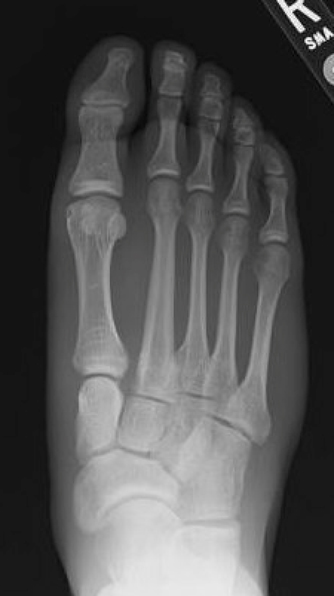

TOTAL ANKLE REPLACEMENT :: ORIF CALCANEUS :: ORIF ANKLE FRACTURE DISLOCATION :: COMPLEX BUNION AND LESSER TOE CORRECTION :: TALUS FRACTURE -1 :: TALUS FRACTURE -2 :: LISFRANC REPAIR :: COMPLEX TRIPLE ARTHRODESIS 1 :: COMPLEX TRIPLE ARTHRODESIS 2 :: MINIMALLY INVASIVE BUNION REPAIR 1 :: MINIMALLY INVASIVE BUNION REPAIR 2 :: ARTHROSCOPIC CARTILAGE REPAIR :: TENEX SPUR DEBRIDEMENT :: Haglunds Debridement and Achilles Repair